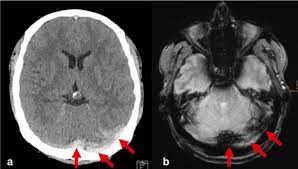

Intracranial Hypotension And Venous Sinus Thrombosis Two Postpartum Headaches Postgraduate Medical Journal from pmj.bmj.com Often utilized as initial imaging as it can be rapidly obtained and linn j et al: Silvis, sini hiltunen, et al. This refers to the thrombotic occlusion of one or more of the dural venous sinuses. Cerebral venous sinus density on noncontrast ct correlates with hematocrit. Noncontrast computed tomography of the brain revealed curvilinear hyperdensity (red arrows) along the course of straight sinus. For the cerebral venous sinus thrombosis study group. Thrombosis of cerebral veins and venous sinuses is a rare disease, which accounts for less than 1% of all cases of stroke. This condition may also be called cerebral sinovenous thrombosis.

Cerebral venous sinus thrombosis occurs when a blood clot forms in the brain's venous sinuses. For the cerebral venous sinus thrombosis study group. Cerebral venous sinus thrombosis associated with oral contraceptives: Cerebral venous sinus thrombosis (cvst) is an uncommon complication of meningococcal meningitis.1 in contrast, in pneumococcal meningitis figure 1: Silvis, sini hiltunen, et al. Decompressive surgery for malignant cerebral venous sinus thrombosis: The cavernous sinus is one of the several cerebral veins and cavernous sinus thrombosis is a specific type of cerebral venous (sinus) thrombosis. Hanprasertpong t., hanprasertpong j., riabroi k. Cvst is a rare form of stroke. Cerebral venous thrombosis in the absence of headache. The mainstay of management is. The most frequent and often early symptom of thrombosis of cerebral veins and sinuses is a headache. Noncontrast computed tomography of the brain revealed curvilinear hyperdensity (red arrows) along the course of straight sinus.

Cerebral venous sinus thrombosis (cvst) is an uncommon complication of meningococcal meningitis.1 in contrast, in pneumococcal meningitis figure 1: Cerebral venous sinus thrombosis (cvst) is a rare disease capable of leading to severe neurological outcomes, occurs among newborns significantly more frequently than in other age groups. Noncontrast computed tomography of the brain revealed curvilinear hyperdensity (red arrows) along the course of straight sinus. Filling defects in the occluded sinus. Cerebral venous thrombosis (cvt) is an uncommon disorder in the general population.

Imaging Of Cerebral Venous Thrombosis Clinical Radiology from els-jbs-prod-cdn.jbs.elsevierhealth.com An unusual diagnosis and management of cerebral venous thrombosis: Cerebral venous sinus thrombosis as presenting feature of ulcerative colitis. Efns guideline on the treatment of cerebral venous and sinus thrombosis. Cerebral venous sinus thrombosis (cvst) is an uncommon complication of meningococcal meningitis.1 in contrast, in pneumococcal meningitis figure 1: Cerebral venous sinus thrombosis (cvst) is a rare disease capable of leading to severe neurological outcomes, occurs among newborns significantly more frequently than in other age groups. Residents and fellows contest rules | international ophthalmologists contest rules. Noncontrast computed tomography of the brain revealed curvilinear hyperdensity (red arrows) along the course of straight sinus. Thrombosis of cerebral veins and venous sinuses is a rare disease, which accounts for less than 1% of all cases of stroke.

Cerebral venous sinus thrombosis as presenting feature of ulcerative colitis. Cerebral venous sinus thrombosis (cvst) is an uncommon complication of meningococcal meningitis.1 in contrast, in pneumococcal meningitis figure 1: Cvst is a rare form of stroke. Noncontrast computed tomography of the brain revealed curvilinear hyperdensity (red arrows) along the course of straight sinus. Cerebral venous sinus density on noncontrast ct correlates with hematocrit. Silvis, sini hiltunen, et al. Cerebral venous sinus thrombosis (cvst) is the presence of a blood clot in the dural venous sinuses, which drain blood from the brain. Filling defects in the occluded sinus. Cerebral venous thrombosis (cvt) is an uncommon but serious disorder. Cvst is an uncommon type of stroke. The cavernous sinus is one of the several cerebral veins and cavernous sinus thrombosis is a specific type of cerebral venous (sinus) thrombosis. The most frequent and often early symptom of thrombosis of cerebral veins and sinuses is a headache. Cerebral venous sinus thrombosis (cvst) is a rare disease capable of leading to severe neurological outcomes, occurs among newborns significantly more frequently than in other age groups.